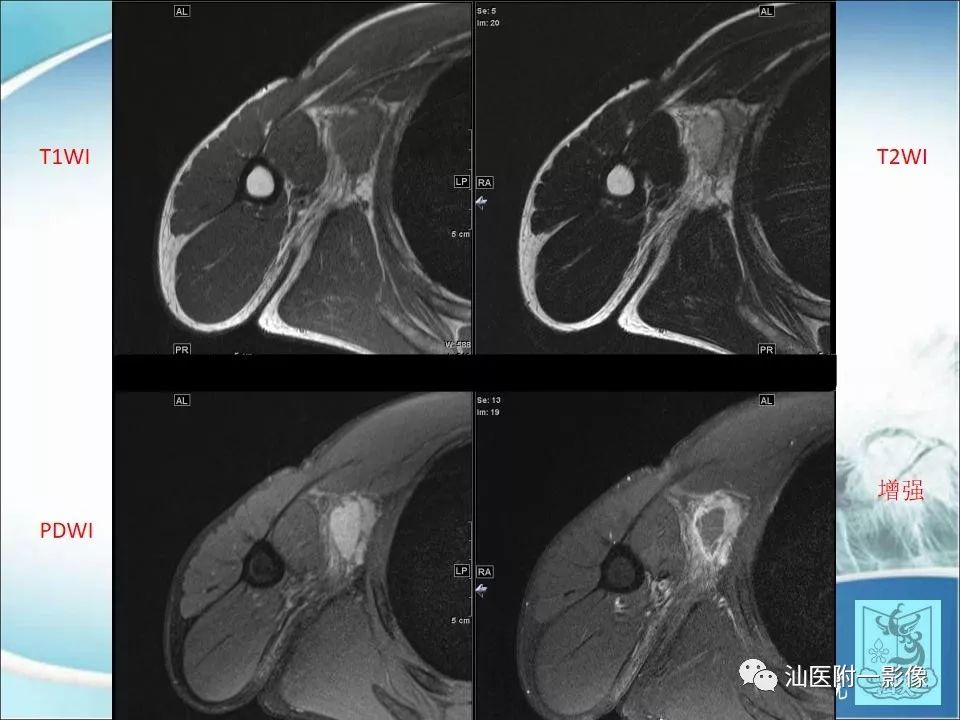

猫抓病1例MR影像

【病例】猫抓病1例MR影像-3